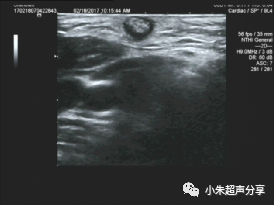

病例4  女 ,15岁,背部毛母质瘤,

其内可见细点状钙化